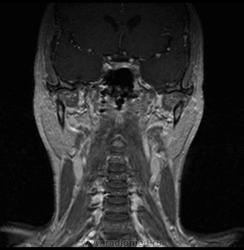

06.06.2011 МРТ - головы и шеи.

Пацентка 36 лет, с жалобами на припухлось в околоушной области справа.

В глубокой доле  правой околоушной железы  на фоне неизмененной паренхимы зона  гетерогенного по Т2, гипоинтенсивного по Т1  с единичными гиперинтенсивными включениями.При контрастировании- накопление контраста диффузное неоднородное и по периферии.Рискну предположить злокачественное образование ( аденокарцинома) с низкой степенью злокачественности( есть капсула, экспансивный рост).Сильно не расстреливайте.

Проблема в том, что перед челюстно-лицевым хирургом стоит распространенность любого объемного процесса, в данном случае все упирается в возмможную травму лицевого нерва и конечно же с дальнейшим его парезом, а ведь женщина  еще молодая. Образование имеет тонкостенную оболочку, по структуре неоднородно, с наличием кальцината, при этом МР-сигнал от окружающих анатомических структур(как костных так и мышечных) не изменен, т.е. об инфильтративном росте речи не идет, в какой то степени доброкачественное. В конкретном случае лицевой нерв с ретромандибулярной веной просто несколько оттеснен.

По гистологии аденома околоушной слюнной железы, но после удаления пока сохраняется парез лицевой мускулатуры, возможно временный.